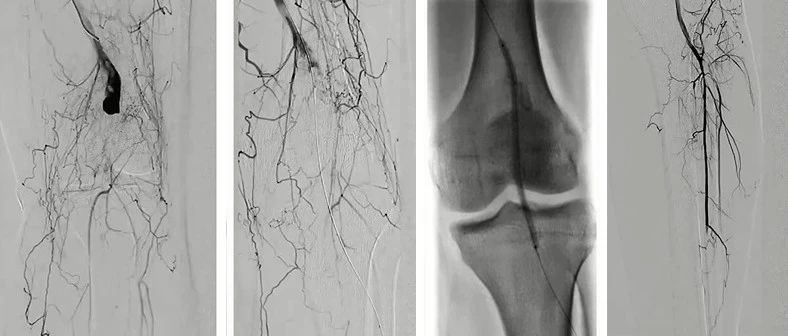

2022 CEC 手术精选 | 熊江:脉管炎腘动脉假性动脉瘤的覆膜支架植入

2022 CEC 手术精选 | 寇镭:Shockwave冲击波导管治疗髂动脉严重钙化病变